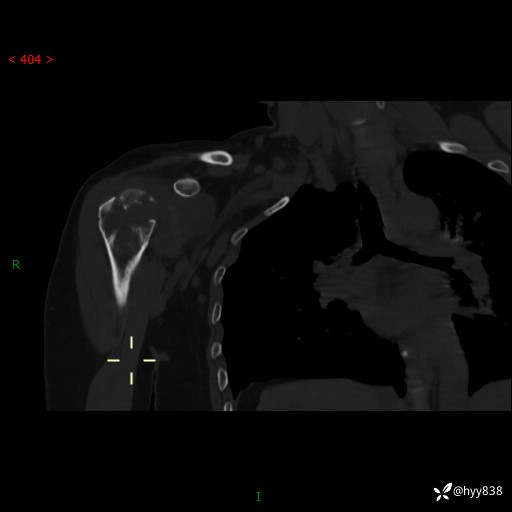

中年女性,发现右肩关节占位2天。有特征、有细节---结果公布~

年龄:47岁

主诉:发现右肩关节占位2天

现病史:患者3年前摔伤致右肩部疼痛,未行特殊处理,后右肩活动时轻度疼痛,患者未引起重视。1月前上述症状加重,于当地县人民医院就诊,2023-07-10右肩关节MR:右肱骨头、肩胛骨及周围软组织异常信号。现患者右肩可触及质硬包块,活动时疼痛,无头晕头痛、恶心呕吐、腹痛腹胀等,为求进一步治疗,来我科就诊,门诊以“右股骨占位性病变”收入我科。 起病以来,患者精神、饮食、睡眠可,大小便正常,体力、体重未见明显变化。

右肩关节CT平扫